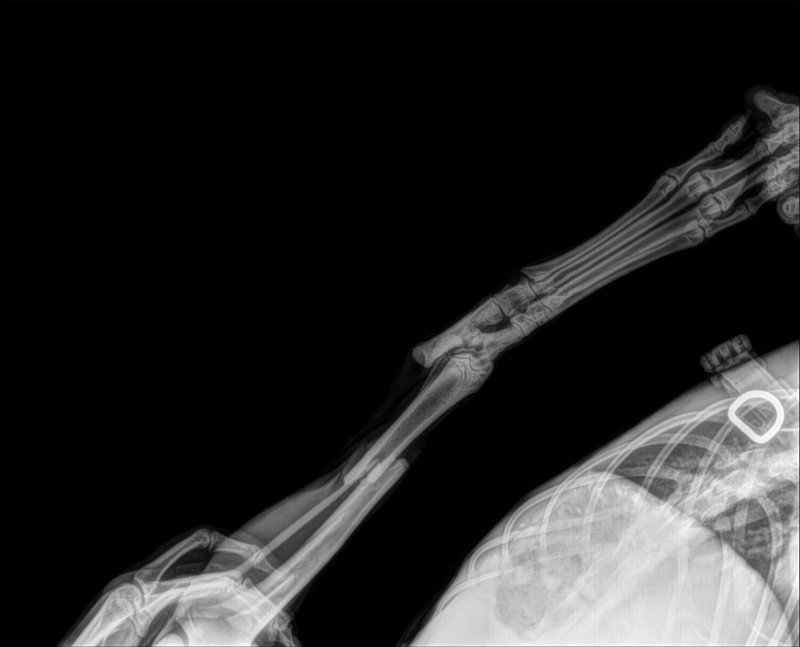

BB MERLIN :

Suite aux radios du 20.12.2024, la consolidation des 2 pattes avance bien. La patte arrière est cicatrisée et l’ossification est ok mais les 2 orthopédistes ont décidé de ne pas enlever le matériel car il n’y a pas d’urgence et le plus important est la patte avant.

L'ostéite (infection de l'os) de la patte avant est stable et la cicatrisation ainsi que l'ossification sont en cours. La patte avant, à cause de l'ostéite,est impossible à opérer ce jour car la consolidation est en cours mais c'est encore bien fragile.

Le prochain RDV est prévu le 6 janvier 2025 et selon les radios des décisions seront probablement prises.

Merlin sera surement opéré de la patte avant à la date du 6 janvier pour enlever la plaque et les vis et mettre une plaque plus petite.

Ils l'ont trouvé très bien au niveau de sa santé générale, et il est très vif et bien dans sa tête.

Vu son cas il ne faut s’occuper que de l’urgence qui est à ce jour la consolidation et cicatrisation de la patte avant.

Soyons optimiste mais la patte avant n’est pas encore sauvée mais c’est en bonne voie. Tout dépendra de l’infection osseuse.